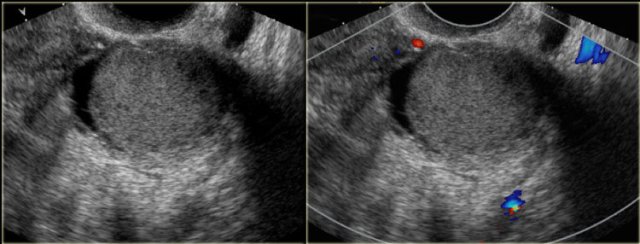

The transvaginal ultrasound images show a small complex ovarian cyst with wall vascularity on power Doppler analysis.

The characteristic circular Doppler appearance is called the 'ring of fire'.

Note, there is good through-transmission and no internal vascularity, consistent with a, partially involuted, corpus luteum cyst.

Another case with the typical the 'ring of fire' on ultrasound.

At pathologic examination the collapsed bloody cyst can be clearly seen.